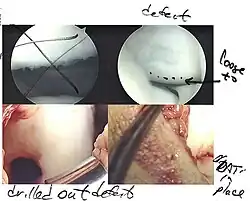

Intact lesions

If non-surgical measures are unsuccessful, drilling may be considered to stimulate healing of the subchondral bone. Arthroscopic drilling may be performed by using an antegrade (from the front) approach from the joint space through the articular cartilage, or by using a retrograde (from behind) approach through the bone outside of the joint to avoid penetration of the articular cartilage. This has proven successful with positive results at one-year follow-up with antegrade drilling in nine out of eleven teenagers with the juvenile form of OCD,[53] and in 18 of 20 skeletally immature people (follow-up of five years) who had failed prior conservative programs.[54]

Hinged lesions

Pins and screws can be used to secure flap (sometimes referred to as hinged) lesions.[55] Bone pegs, metallic pins and screws, and other bioresorbable screws may be used to secure these types of lesions.[56]